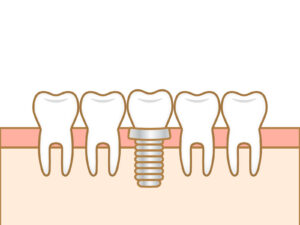

インプラントと矯正治療の関係

インプラントに関する合併症と対処法(最近、話題のクラニオフェイシャルグロースも)

インプラントの寿命に関係する?〜お掃除方法について〜

即時インプラント(最新のルートメンブレンテクニック)

歯周病とインプラントの怖い関係・・・

インプラント・ブリッジの前に、歯の移植を考えましょう

麻酔の4つのこだわり〜35Gの極細針を使用〜

マイクロスコープを用いた低侵襲手術

美しく・長持ちするコンポジットレジン修復を目指して

即時入れ歯(インプラントを支えに入れ歯を即時で固定する治療法)